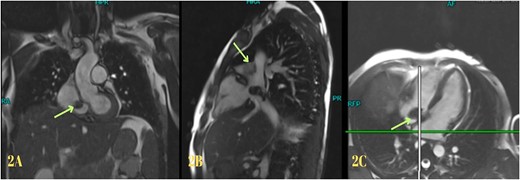

Blood investigations revealed leukocytosis and thrombocytopenia (Table 1). His electrocardiogram (ECG) showed a normal sinus rhythm, and chest X-ray revealed bilateral infiltrates. A high-resolution computed tomography (HRCT) scan of the chest was done in February 2020, which showed multiple patchy pulmonary infiltrates in the upper and lower lobe of the left lung, the middle lobe and the lower lobe of the right lung (Fig. 1). An air bronchogram was noted within the area of consolidation of the middle lobe of the right lung. Also, heavy calcification of irregular areas within the right atrium, extending up to the opening of the IVC, was noted. We did a further investigation with transthoracic echocardiography, which revealed an echogenic mass in the right atrium of 3.0 ✕ 1.9 cm2, most likely a thrombus. Following this, we investigated the patient with cardiac MRI, which showed a large irregular mass of 25 ✕ 18 mm2 in the right atrium attached to the interatrial septum and extending to the IVC, most likely myxoma with superimposed thrombus (Fig. 2).